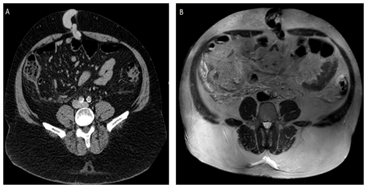

Ultrasound performed in attendance reveals ascites, signs of chronic liver disease and portal hypertension, such as splenomegaly, dilated splenic and portal veins, and recanalization paraumbilical vein that presents with herniated fat content. This vascular herniated segment presents thrombosed (Figure 2). After the ultrasound, the umbilical hernia was reduced manually, and patient was removed to the ICU.

Figure 2 In A, ultrasound demonstrating recanalization of the herniated paraumbilical vein. In B, ultrasound demonstrating herniated paraumbilical vein segment without vascularization to Doppler - thrombosis.